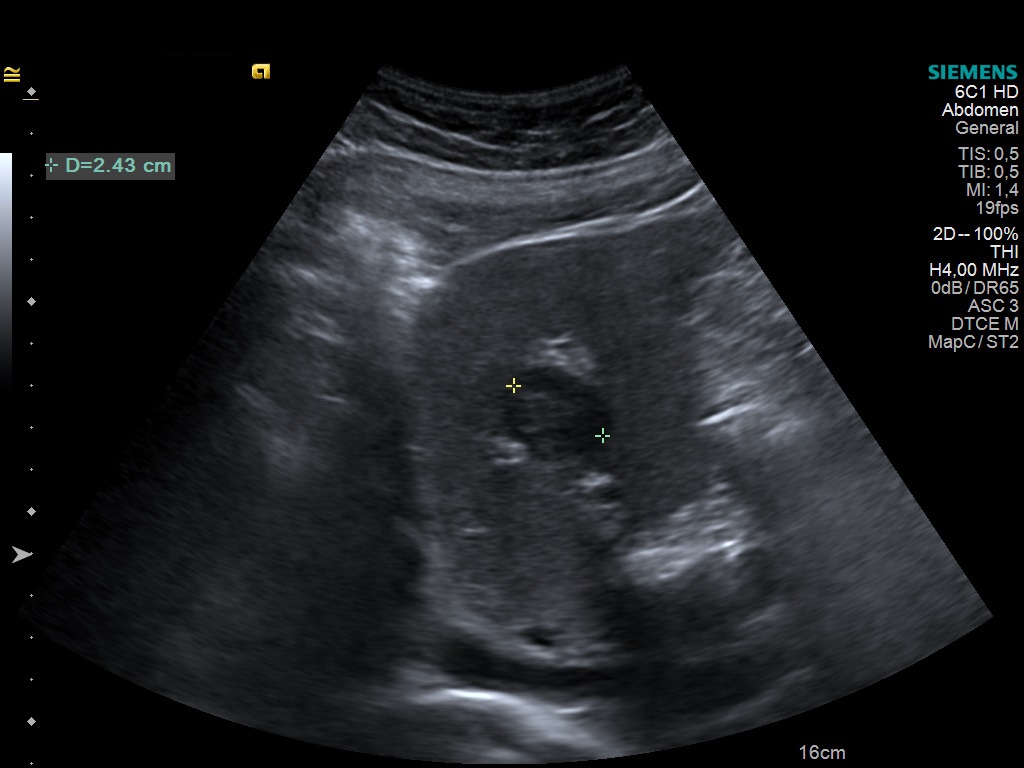

Correct! focal nodular hyperplasia

In B-mode, the hepatic lesion appears irregular shaped and hypoechoic. With contrast-enhanced ultrasound the lesion becomes hyperdense, with centrifugal filling during the hepatic arterial phase and sustained enhancement in the portal venous phase (as opposed to adenoma).